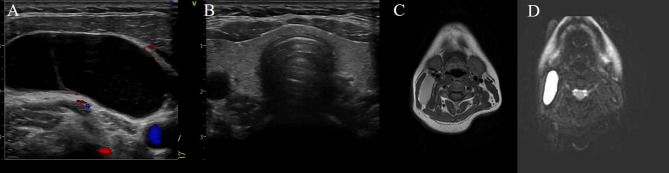

Case presentation: A 33-year-old Chinese woman presented to the hospital with an incidental mass in her right neck. Ultrasonography and magnetic resonance imaging revealed a giant right cystic mass in the inferior submandibular gland. The patient underwent mass dissection. Histopathological assessment indicated metastatic papillary carcinoma from the thyroid. Total thyroidectomy and bilateral selective neck dissection were performed. Meticulous pathological examination revealed no lesions in the thyroid. After 18 months of follow-up, no signs of recurrence were noted.